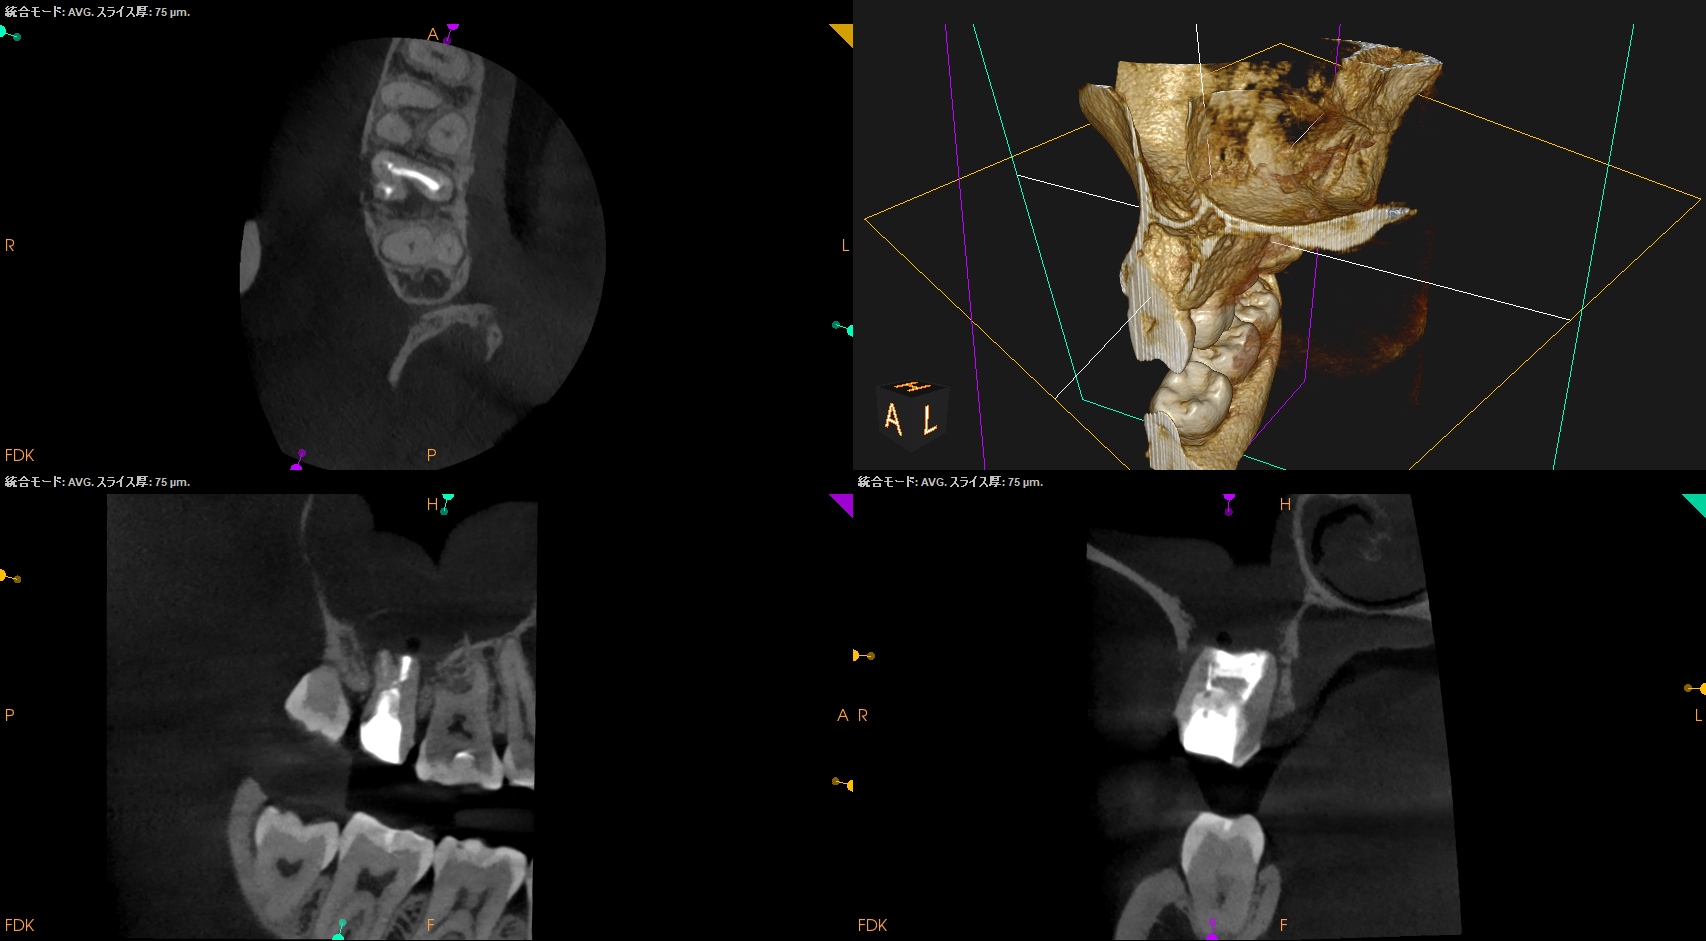

CBCT(2025.11.11)

MB

DB

P

根管は石灰化&すでに拡大済みであるので、再根管治療ではなく外科治療、つまり、Intentional Replantationの適応症である。